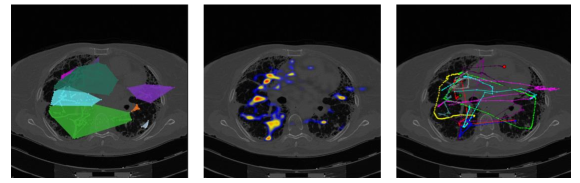

3.2.2 Lung cancer screening experiment:

In the lung cancer screening experiments, our participants examined volumetric chest CT scans and the corresponding data was recorded in 3D space. The qualitative results and comparison of visual search patterns of the three radiologists are reported in Fig. 9. Each column shows one step of the proposed algorithm and each row corresponds to a radiologist. As can be seen, dense graphs hardly reveal any comparisons between radiologists’ visual search patterns. However, it is much easier to use sparsified graph (last column) for a global comparison of visual search pattern.

One of our participating radiologists, an expert in prostate cancer screening, examined multi-parametric MRI (four 3D images) for routine prostate cancer screening. Based on the results reported in Fig. 16, it is evident by the sparsified graphs that the radiologist used axial T2-weighted images (anatomical information) and ADC maps (showing magnitude of diffusion) more frequently than other two images. This observation suggests that although all four modalities are being used for making a diagnostic decision T2-weighted and ADC map are more informative to the radiologists in the screening process. This observation can be useful in further developments of automatic computer-aided diagnosis systems.

Quantitative results of our method for different modalities as well as the variation over these modalities are shown in Fig. 16 and Fig. 17, respectively. In screening, DWI and DCE modalities were used less frequently than T2-weighted and ADC modalities; therefore, the initial graph representations of the DWI and DCE are less dense compared to those of T2-weighted and ADC. For those less dense graphs, the sparsification algorithm achieved a similar MSE performance in most edge ratios larger than 0.5. From the reason that the sparsification algorithm keeps the graph in a of the original graph, we cannot remove large number of edges from less dense graphs. This situation is reflected in diameter ratio and betweenness metrics.

As can be interpreted from the lung screening experiment, the less experienced participant had more crowded visual search patterns and examined the most lung volume. Also, from the prostate cancer screening experiment, we observed that radiologists use anatomical/structural information more frequently than other modalities in screening (i.e., diffusion MRI). This potentially shows the importance of anatomical information in prostate cancer detection but at the same time we noticed that when anatomical information gives less clues to radiologists about potential abnormality, radiologists looks for complementary information from other imaging modalities to make inference. Our system provides visualization of this process for the first time in the literature. Scanpaths across different screens prove this observation as can be seen in Fig. 16.